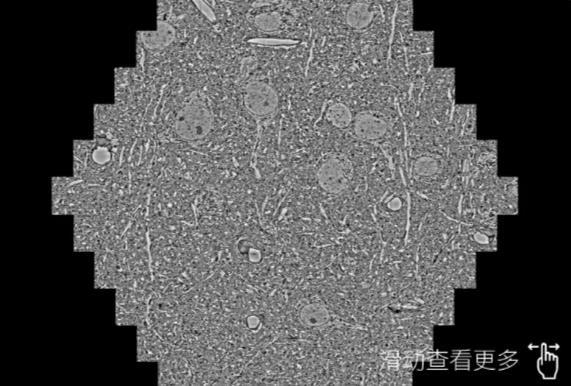

鼠脑切片。左图使用佛山蔡司佛山扫描电镜MultiSEM706对165μmx143pm面积区域成像,耗时仅需1.5秒。右图为鼠脑切片中30μm区域放大效果。样品由芝加哥大学B.Kasthuri提供。

使用蔡司高速佛山扫描电镜MultiSEM对1mm²人脑皮层组织进行高分辨成像,并对其中的各种细胞结构进行三维重构分析。左图展示了2x3mm²组织平面中锥体神经元的三维重构效果。右图显示了局部体积神经元三维重构。图像由哈佛大学chtman实验室提供,渲染图由D. Berger 制作。